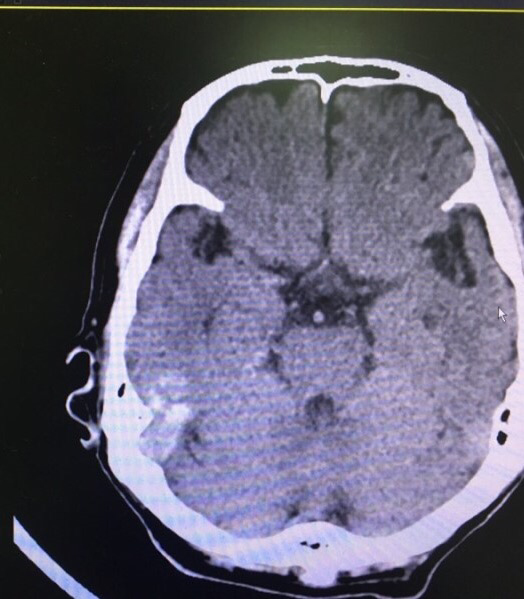

어지럼증 호소하는 60세 남성.

CT 상 우측 측두엽이 이상하다.

우측 측두엽이 하얗다.